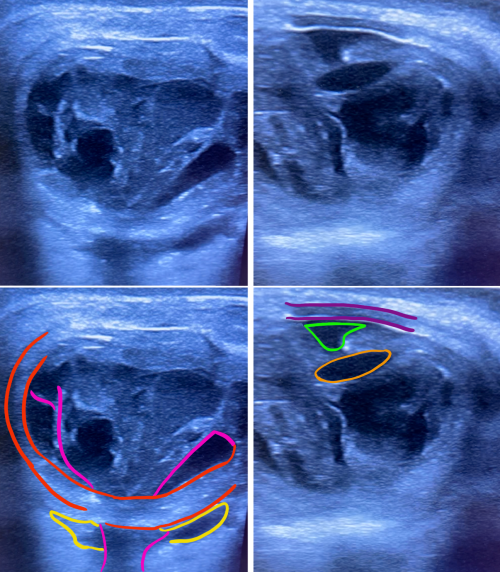

When an infectious etiology is suspected in the orbit, dilated fundus exam is deferred as it would interfere with identifying a new afferent pupillary defect, a critical orbital sign suggestive of progression. A Bright Scan Ultrasound (B-scan) can be used to visualize the posterior chamber of the eye to assess for vitritis (vitreous inflammation that present as vitreous echoes), exudative retinal detachment, scleritis (scleral thickening with classic “T-sign”), choroidal lesions (dome-shaped lesions), choroidal thickening, sub-tenon’s fluid, lens dislocation, lens edema, and shallow anterior chamber).

Bright-scan Ultrasonography (B-Scan)

B-Scan is a cost-effective, efficient modality to evaluate posterior segment lesions of the eye. It is particularly useful for assessment of the vitreous, posterior pole, sub-tenon’s space.